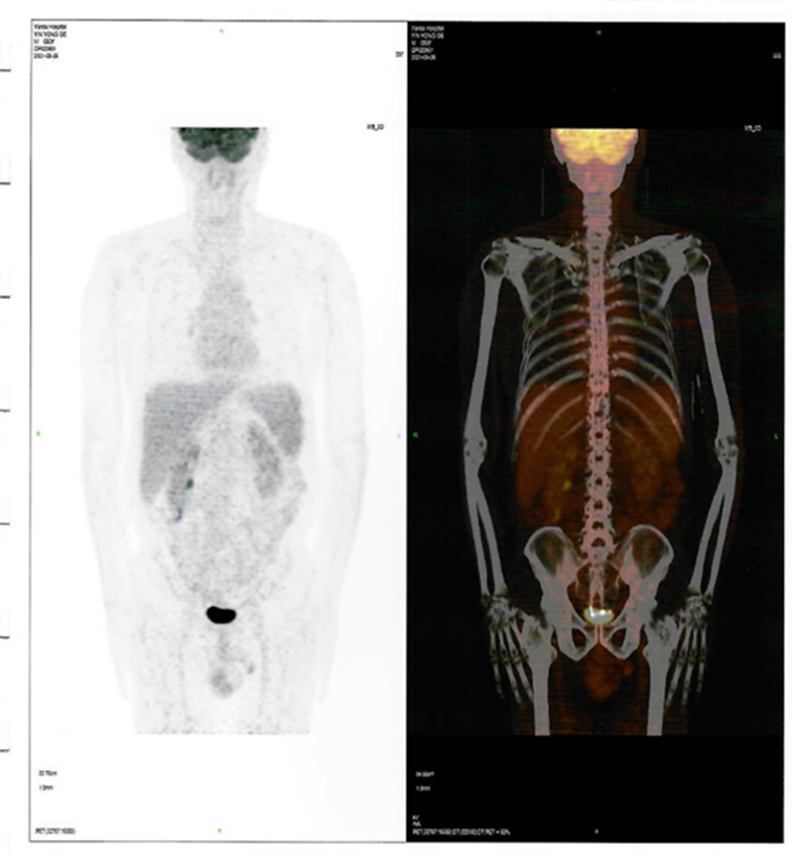

患者CAR-T 前后PET-CT檢查結果對比圖

CAR-T治療后30天

回輸后一度出現(xiàn)了一級CRS反應,癥狀可控,5月26日,回輸后+28天復查PET-CT顯示CR(完全緩解)。預祝黃山先生接下來的治療一切順利!